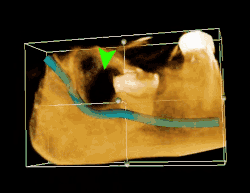

| 3D CT of an impacted wisdom tooth adjacent the inferior alveolar nerve prior to removal of wisdom tooth | |

If the tooth cannot be assessed with clinical exam alone, the diagnosis is made using either a panoramic radiograph or cone-beam CT. Where unerupted wisdom teeth still have eruption potential several predictors are used to determine the chance of the teeth becoming impacted. The ratio of space between the tooth crown length and the amount of space available, the angle of the teeth compared to the other teeth are the two most commonly used predictors, with the space ratio being the most accurate. Despite the capacity for movement into early adulthood, the likelihood that the tooth will become impacted can be predicted when the ratio of space available to the length of the crown of the tooth is under 1.[5]: 141

Long-term complications can include periodontal complications such as bone loss on the second molar following wisdom teeth removal. Bone loss as a complication after wisdom teeth removal is uncommon in the young but present in 43% of those of 25 years of age or older.[23] Injury to the inferior alveolar nerve resulting in numbness or partial numbness of the lower lip and chin has reported rates that vary widely from 0.04% to 5%.[23] The largest study is from a survey of 535 oral and maxillofacial surgeons in California, where a rate of 1:2,500 was reported.[26]

Coronectomy is a procedure where the crown of the impacted wisdom tooth is removed, but the roots are intentionally left in place. It is indicated when there is no disease of the dental pulp or infection around the crown of the tooth, and there is a high risk of inferior alveolar nerve injury.[32]